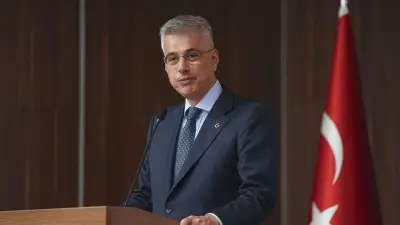

Uzman Uyarısı: "Çöl Tozları Masum Değil"

Göğüs Hastalıkları Uzmanı Dr. Öğr. Üyesi Seha Akduman, çöl tozlarının yalnızca kum taneciklerinden oluşmadığını vurgulayarak şu açıklamayı yaptı: "Yapılan araştırmalar, bu partiküllerin akciğer dokusunda hücrelere zarar veren ve iltihaplanmayı artıran bir etki oluşturduğunu gösteriyor. Tozlar, ağır metaller, polenler ve mikroorganizmalar taşıyabiliyor. Bu tozlar, solunum yoluyla akciğerlerin en derin noktalarına kadar ulaşıyor."

Dr. Akduman, toz taşınımının etkili olduğu dönemlerde acil servis başvurularında artış yaşandığını belirtti. "Güncel bilimsel çalışmalar, yoğun toz maruziyetinin yalnızca astım ve KOAH gibi mevcut solunum hastalıklarını tetiklemediğini, sağlıklı bireylerde bile yeni tanılı astım gelişimine zemin hazırlayabildiğini gösteriyor" diye ekledi. Hava yollarında oluşan hassasiyet ve iltihaplanmanın, toz bulutları dağıldıktan sonra dahi haftalarca sürebileceği uyarısında bulundu.

Özellikle çocuklar, yaşlılar ile kalp ve akciğer hastalarının bu süreçte daha dikkatli olması gerektiğini vurgulayan Dr. Akduman, çöl tozunun etkili olduğu günlerde alınabilecek önlemleri şöyle sıraladı: